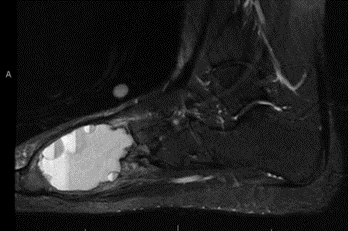

Αφού εξετάσει τις ακτινογραφίες, ο γιατρός μπορεί να παραγγείλει μαγνητική τομογραφία (MRI) ή, σε πολύ σπάνιες περιπτώσεις, αξονική τομογραφία (CT).

Μαγνητική τομογραφία (MRI). Οι σαρώσεις μαγνητικής τομογραφίας βοηθούν τους γιατρούς να προσδιορίσουν πού αρχίζει και πού τελειώνει ο όγκος, γεγονός που τους βοηθά να σχεδιάσουν τη θεραπεία.

Ενώ οι αξονικές τομογραφίες είναι καλύτερες στην απεικόνιση του οστού, οι μαγνητικές τομογραφίες είναι οι καλύτερες για την εξέταση του ιστού και του υγρού μέσα στην κύστη. Η κλασική εμφάνιση μιας ανευρυσματικής κύστης στην μαγνητική τομογραφία δείχνει επίπεδα υγρού-υγρού που αντιπροσωπεύουν αίμα και κυστικό υγρό που βρίσκονται σε στρώσεις στον όγκο των οστών.